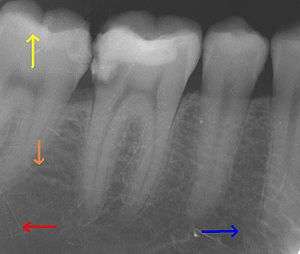

This X-ray film depicts some of the teeth in the lower right quadrant. The arrows point in the following directions: distal , mesial , coronal , apical .